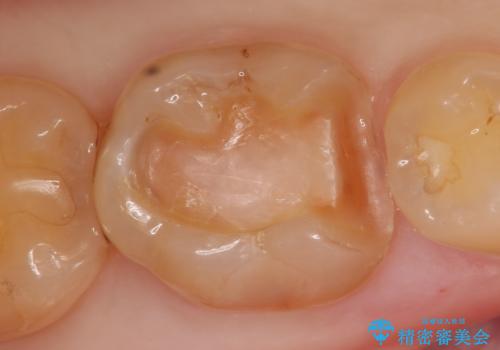

銀歯を除去し、セラミックインレーによる修復を行いました。

当院のセラミックインレーはemaxという強度と審美性に優れた材料を使用しています。

またプレス方式でインレーを製作しているため、削り出しで製作するCADCAMより優れた適合性も持ち合わせており、虫歯が再発しにくい修復物です。